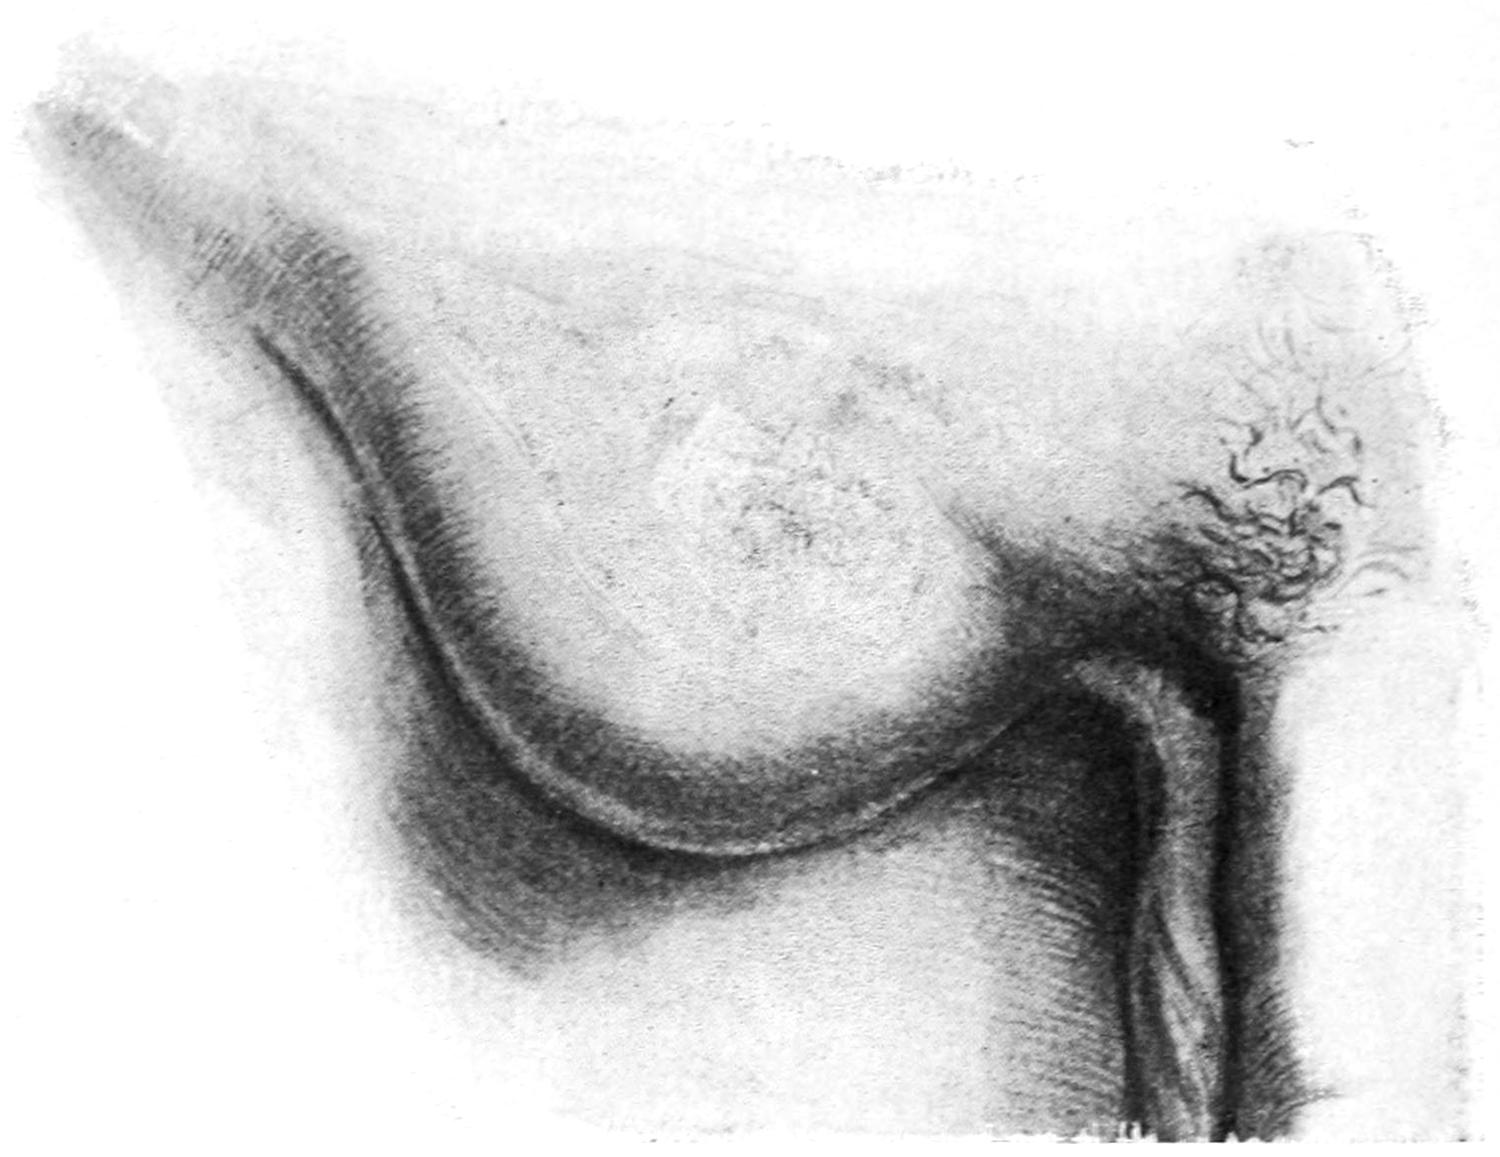

Fig. 1

Congenital hypertrophy: gigantism of both lower extremities. (Case of Dr. Graefe [Sandusky].)